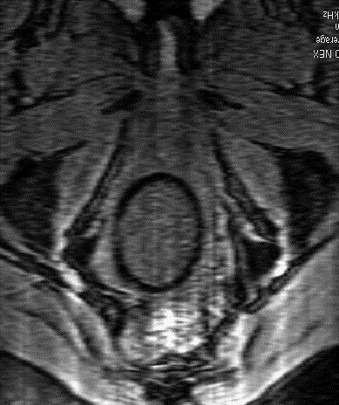

NUVARING PLACEMENT PICTURE